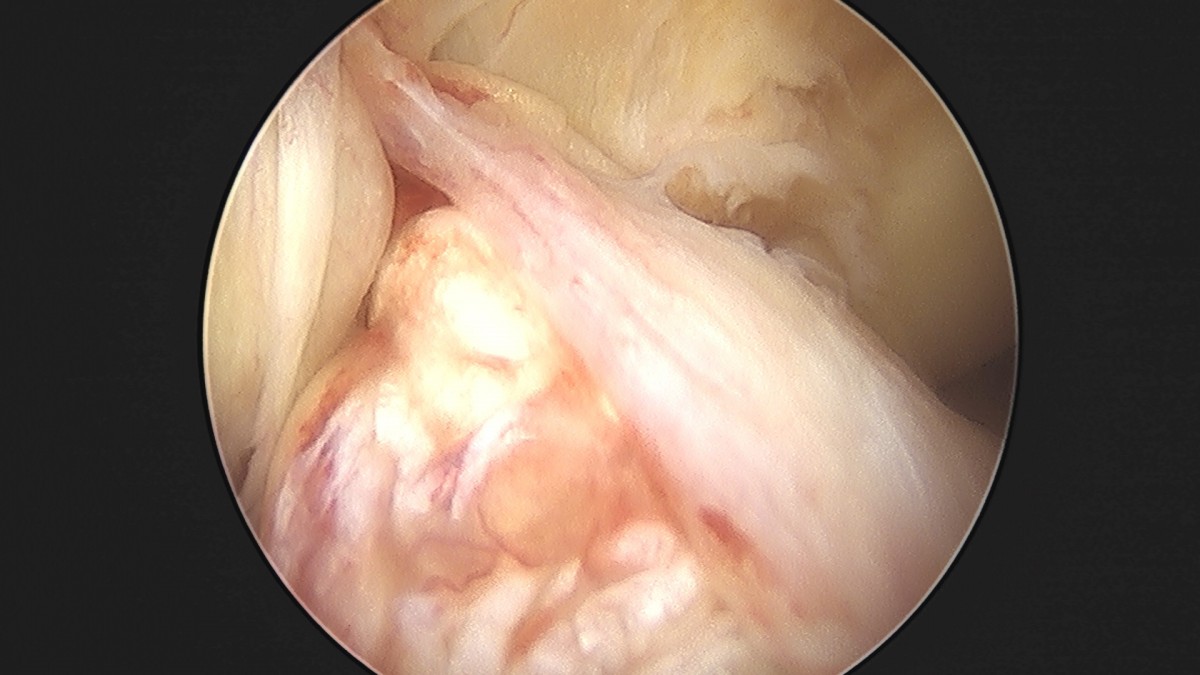

이재상원장님 전방십자인대 재건술 및 반월상 연골판 봉합술 윤두O 환자

작성자 최고관리자 댓글 0건 조회 704회 작성일 25-09-16 16:22